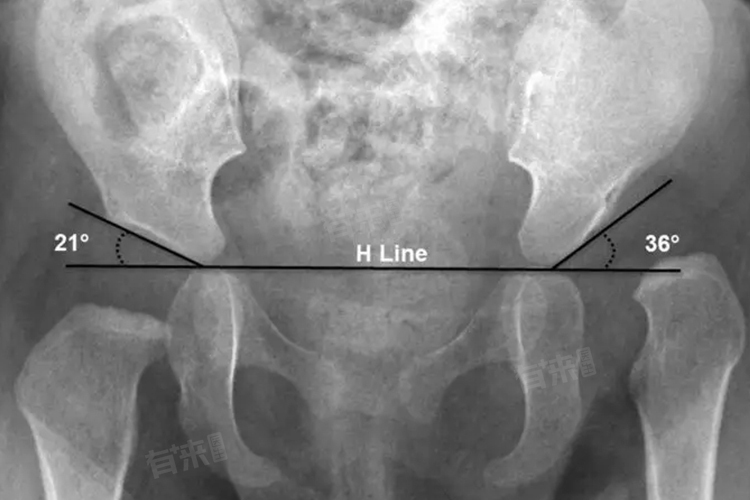

4、Hilgenreiner线与股骨头关系:

Hilgenreiner线作为重要参考线,正常情况下,股骨头骨骺中心应位于由Hilgenreiner线和通过髋臼外上缘所作垂线组成的内下象限内。若X线显示股骨头骨骺中心向上、向外移位,超出该象限范围,则提示存在髋关节半脱位或脱位,可据此判断髋关节发育不良的严重程度。